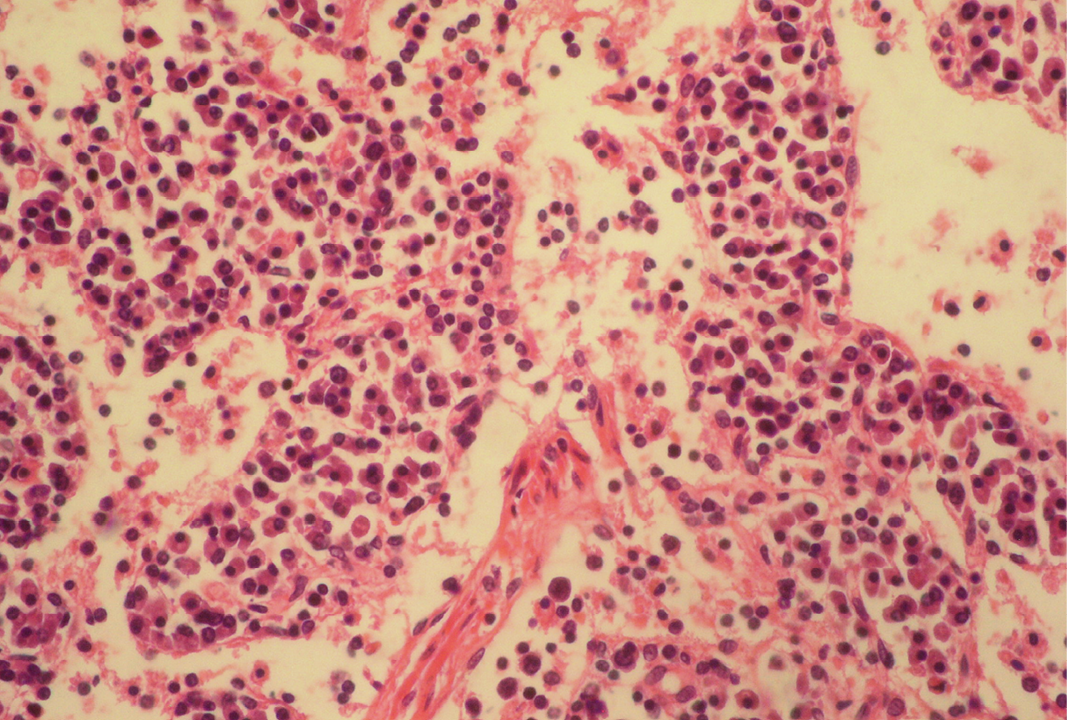

Infiltration of more plasma cells in medullary area

Fibrin threads are found throughout the medulla with lymphoid depletion; H&E x400